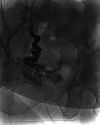

A known consequence of portal hypertension is the development of varices, which are described as "ectopic" when located at unusual sites in the abdomen. Ectopic varices carry a mortality rate as high as 40% after initial hemorrhagic episode. We report a patient who presented with hematuria secondary to bladder varices as the presenting symptom for a new diagnosis of cirrhosis. Cross-sectional imaging, early recognition of this rare event, combined with multidisciplinary management was essential for this patient to have a successful outcome.